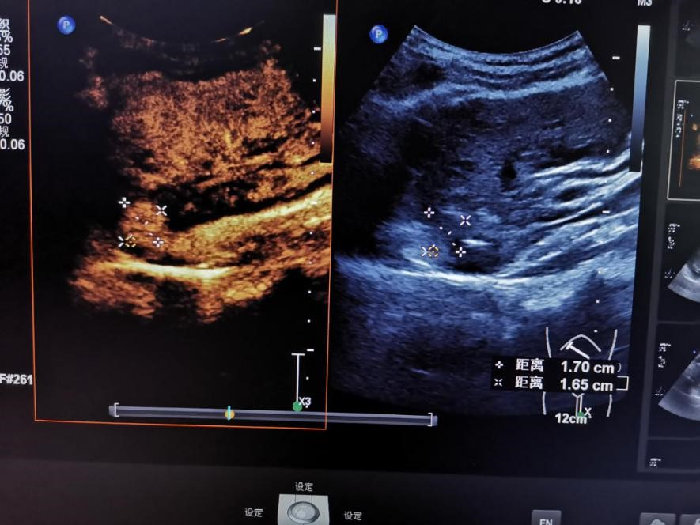

超声诊断科介入组反复比对MRI所示病灶部位,在二维超声确定病灶位置后行超声造影检查,该结节大小1.7cm×1.6cm,属于LI-RADS-5类,即确诊的HCC。该结节位置凶险,位于肝脏S7段边缘,紧贴下腔静脉和膈肌,想要实现精准完全消融十分困难。怎么办?王涛医师提出“火攻+水攻”的策略:低功率微波消融HCC主体病灶,临近大血管处用聚桂醇液补充化学消融。聚桂醇为血管硬化剂,能破坏肿瘤内血管导致其纤维化,同时不会因为热传导伤及周边重要血管。介入组经过认真研究,制定了完备的手术预案。

病灶微波消融术前造影,呈高增强